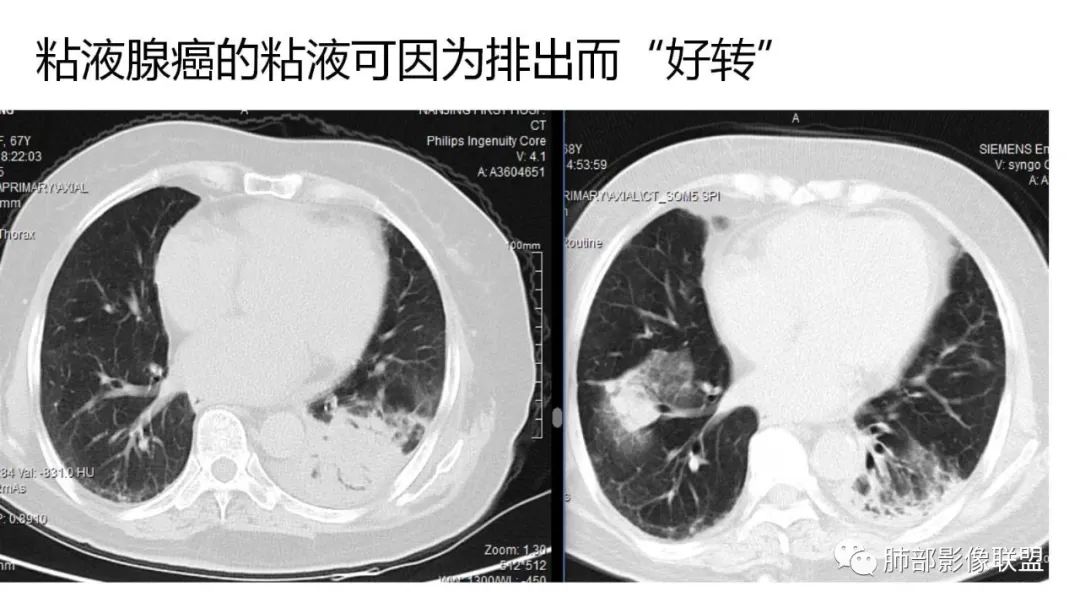

9.粘液腺癌的变化规律:结节缓慢发展而来,向周围播散形成斑片后可快速进展,有时支气管镜后或粘液排出后局部可形成好转的假象。病灶可沿肺泡和支气管播散。

4.回到本例,左下肺病变两次好转,均未经过肿瘤治疗,第一次是支气管镜后,第二次是当其他病变都在进展的情况下,左下肺病变范围反而缩小趋于浅淡。